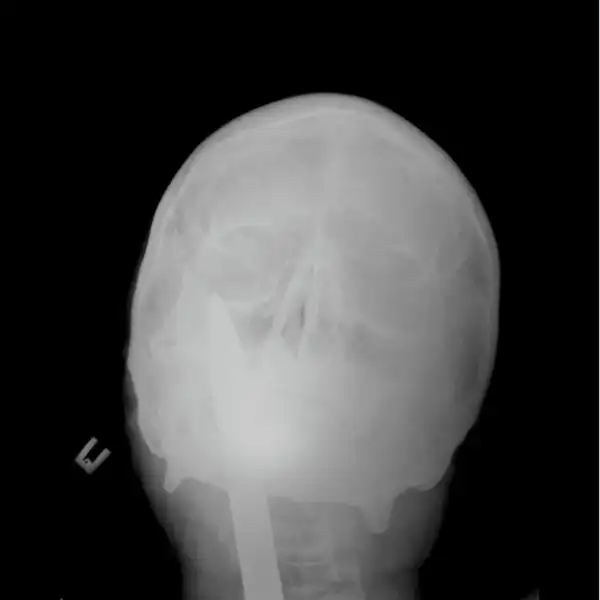

Мужчина упал на лом не повредив жизненно важных органов, говорят после операции выписан в удовлетворительном состоянии домой.